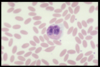

Name this WBC

Neutrophil